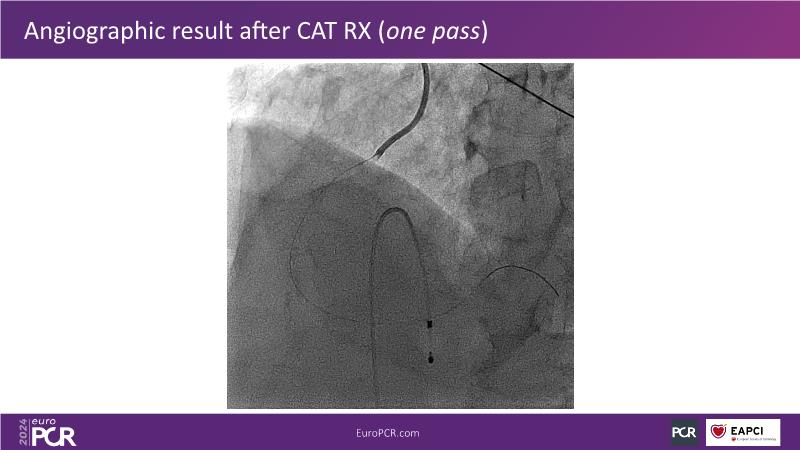

Tune into this 2024 session for insights into the latest ESC guidelines, strategies to prevent and treat no reflow, and an examination of trials like TASTE, TAPAS, and TOTAL on coronary thrombus management. Explore also the outcomes of the CHEETAH study, pondering a potential paradigm shift, and delve into a case study on thrombus removal in a patient with high thrombus burden.